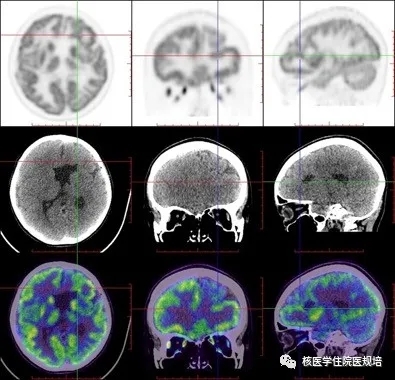

FDG PET/CT脑断层图像示:脑中线结构居中,双侧大脑皮层FDG摄取失常态,MRI所示皮层下带状灰质异位区域可见弥漫性条带状异常FDG摄取,而正常脑灰质区FDG摄取相对略减低,但皮层下核团、小脑放射性分布未见明确异常;同机CT示上述灰质异位区呈等密度改变,同时见双侧侧脑室枕角增宽,脑沟、裂及池形态未见异常。

双侧大脑皮层下弥漫性FDG代谢增高带伴脑室扩大,可符合皮质下层状灰质异位表现。

虽然目前FDG PET/CTDCS的诊疗作用尚无定论,但作为解剖影像的有效补充,可以从功能方面显示异位灰质的葡萄糖代谢情况,不仅有助于帮助观察脑灰质异位的部位及累及范围(图45,图6),还可显示全脑皮层及皮层下核团的代谢信息;此外,若将葡萄糖代谢研究与脑电生理研究结合,可能还会对异位灰质的诊疗提供更多有价值的信息。